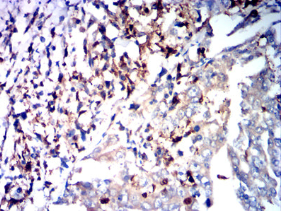

IHC    1/200 - 1/1000